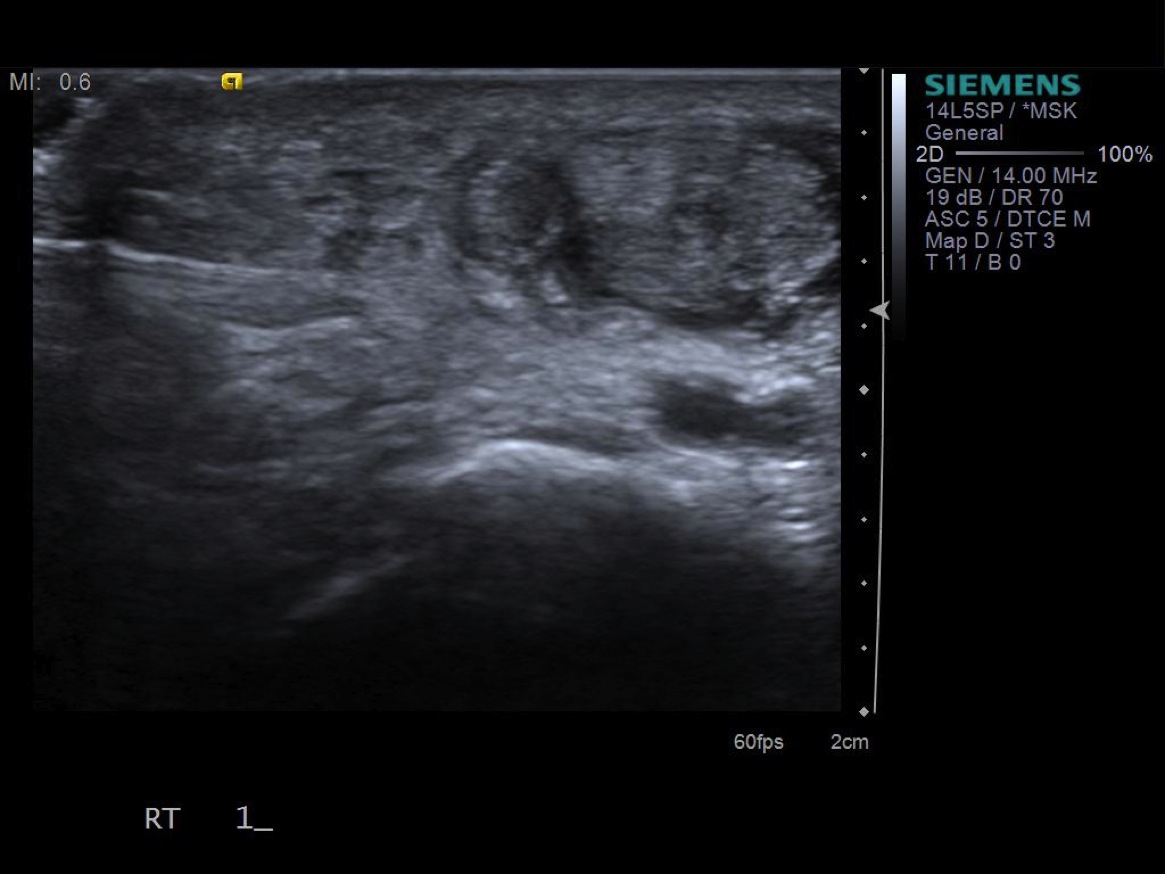

7. Under ultrasound guidance,advance needle into the 1st extensor tendon sheath. In this case the APL and EPB have separate sheaths and require their own injections. Test inject with 1% lidocaine. If no resistance, switch 1% lidocaine for injectable steroid mixture. If there is resistance, reposition needle and test inject again. Inject 1 cc of injectable steroid/anesthetic mixture.